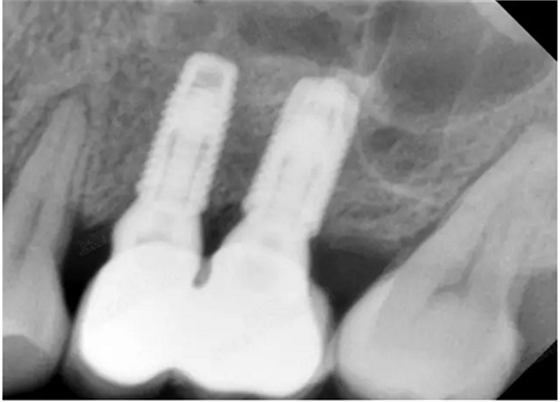

病例一

上頜竇多分隔3mm

05.png

提升8mm

06.png

07.png

修復(fù)時(shí)根尖片

08.png

09.png